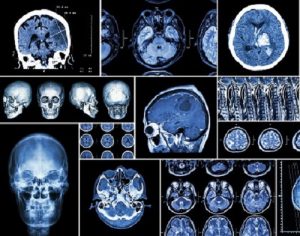

Программа диагностики может включать следующие процедуры:

- Позитронно-эмиссионная томография с КТ.

- Магнитно-резонансная томография.

- Компьютерная томография.

- Однофотонная эмиссионная компьютерная томография.

- Биопсия.

- Развернутые анализы крови.

- Ангиография сосудов головного мозга.

- Люмбальная пункция и другие.